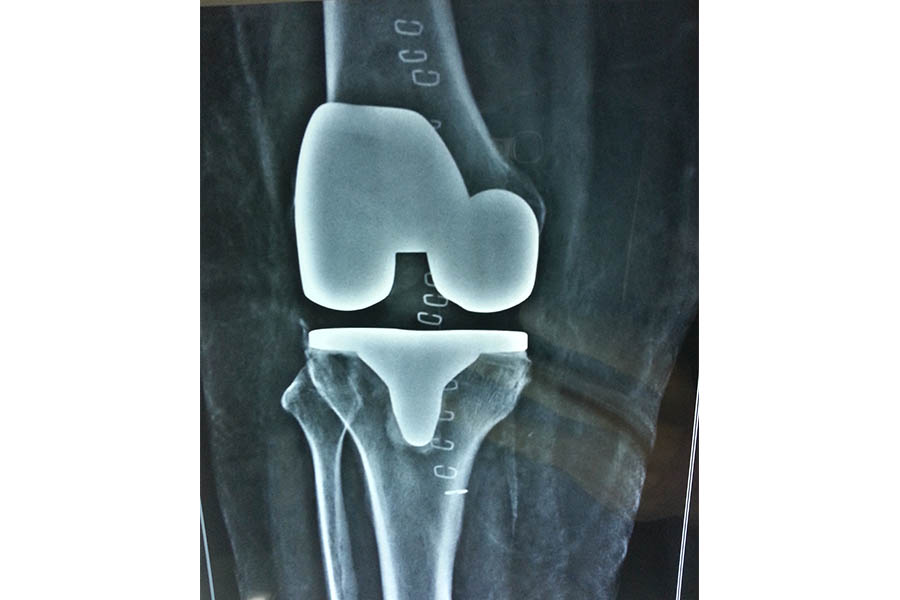

Total Knee Replacement